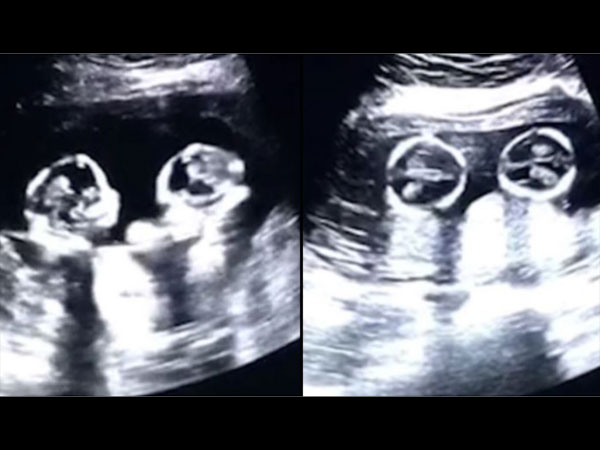

കുട്ടികള് തമ്മില് വഴക്കിടുന്നത് സാധാരണമാണ്. എന്നാല് ഇരട്ടക്കുട്ടികള് തമ്മില് വയറ്റില് കിടന്ന് തന്നെ നല്ല അടിയാണ്. ഇരട്ടക്കുട്ടികള് ആണ് ഗര്ഭത്തില് എന്ന് അറിയുമ്പോള് തന്നെ എല്ലാവര്ക്കും സന്തോഷമാണ്. എന്നാല് ഇപ്പോള് വൈറലായിക്കൊണ്ടിരിക്കുന്ന ഒരു വീഡിയോക്ക് പിന്നില് വയറ്റില് കിടന്ന് അടി കൂടുന്ന രണ്ട് കുട്ടികളുടെ സ്കാനിംഗ് റിപ്പോര്ട്ട് ആണ് പുറത്ത് വന്നിട്ടുള്ളത്.

ഇപ്പോള് തന്നെ ഇത്തരത്തില് ബഹളമാണെങ്കില് പുറത്ത് വരുമ്പോള് എന്തായിരിക്കും അവസ്ഥ എന്ന കാര്യം പറയേണ്ടതില്ലല്ലോ? നല്ല അടിയിലാണ് രണ്ട് മക്കളും. ഇന്ന് ലോകമെമ്പാടും ഇതിന്റെ വീഡിയോ പ്രചരിച്ച് കൊണ്ടിരിക്കുകയാണ്. പലപ്പോഴും ഇത്തരം കാര്യങ്ങളെക്കുറിച്ച് പലരും വളരെ കൗതുകത്തോടെ തന്നെയാണ് കാണുന്നത്. ഈ ഇരട്ടക്കുട്ടികളുടെ അടി വിശേഷങ്ങളെക്കുറിച്ച് നമുക്ക് നോക്കാം. എന്താണ് ഇവര് ചെയ്യുന്നത് എന്ന് നോക്കാം.

എന്നാല് പരസ്പരം വഴക്കടിക്കുന്ന ഗര്ഭസ്ഥശിശുക്കളെയാണ് ഇവിടെ സ്കാനിംഗില് ഡോക്ടര് കണ്ടത്. നിമിഷ നേരം കൊണ്ട് തന്നെ ഈ വീഡിയോ ലോകമെമ്പാടും വൈറലായി. കുട്ടികളുടെ അച്ഛന് തന്നെയാണ് ഇത്തരത്തിലുള്ള ഈ വീഡിയോ സോഷ്യല് മീഡിയയില് പങ്കു വെച്ചത്.